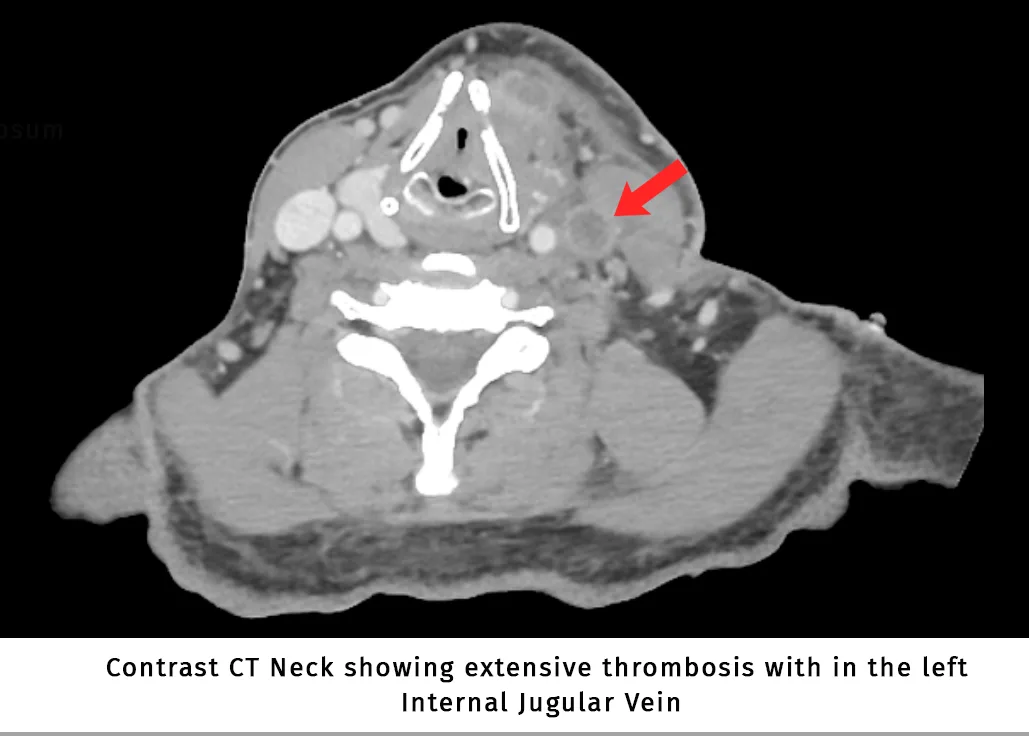

Lemierre’s syndrome

Lemierre’s syndrome (also known as postanginal septicemia) is a rare, life-threatening complication of oropharyngeal / deep neck space infections (parapharyngeal abscess, retropharyngeal abscess etc..) with significant mortality. It is the septic […]